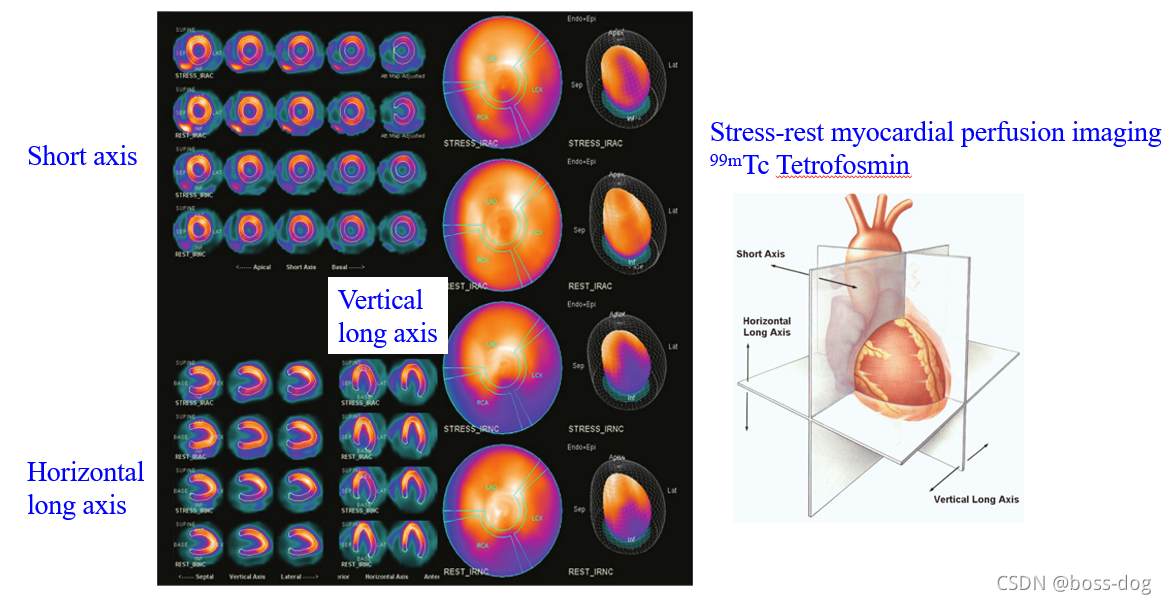

Gamma Camera/Scintillation Camera(核素成像)

心脏成像

4.核素成像(Radionuclide imaging)。有核辐射,需要采用高能量的X光或者伽马光子;应用领域如单光子平面或成像(Planar single photon imaging)、单光子发射的CT(Single Photon EmissionCT,SPECT)、正电子发射成像(Positron Emission Tonography),这三类都是需要通过往人体里面进行静脉注射一种核素,这种核素需要释放出光子或者释放出正电子来回到它的稳态,如果释放出光子,这光子高能光子穿过人体就会被探测器接收到,然后用来做成像。